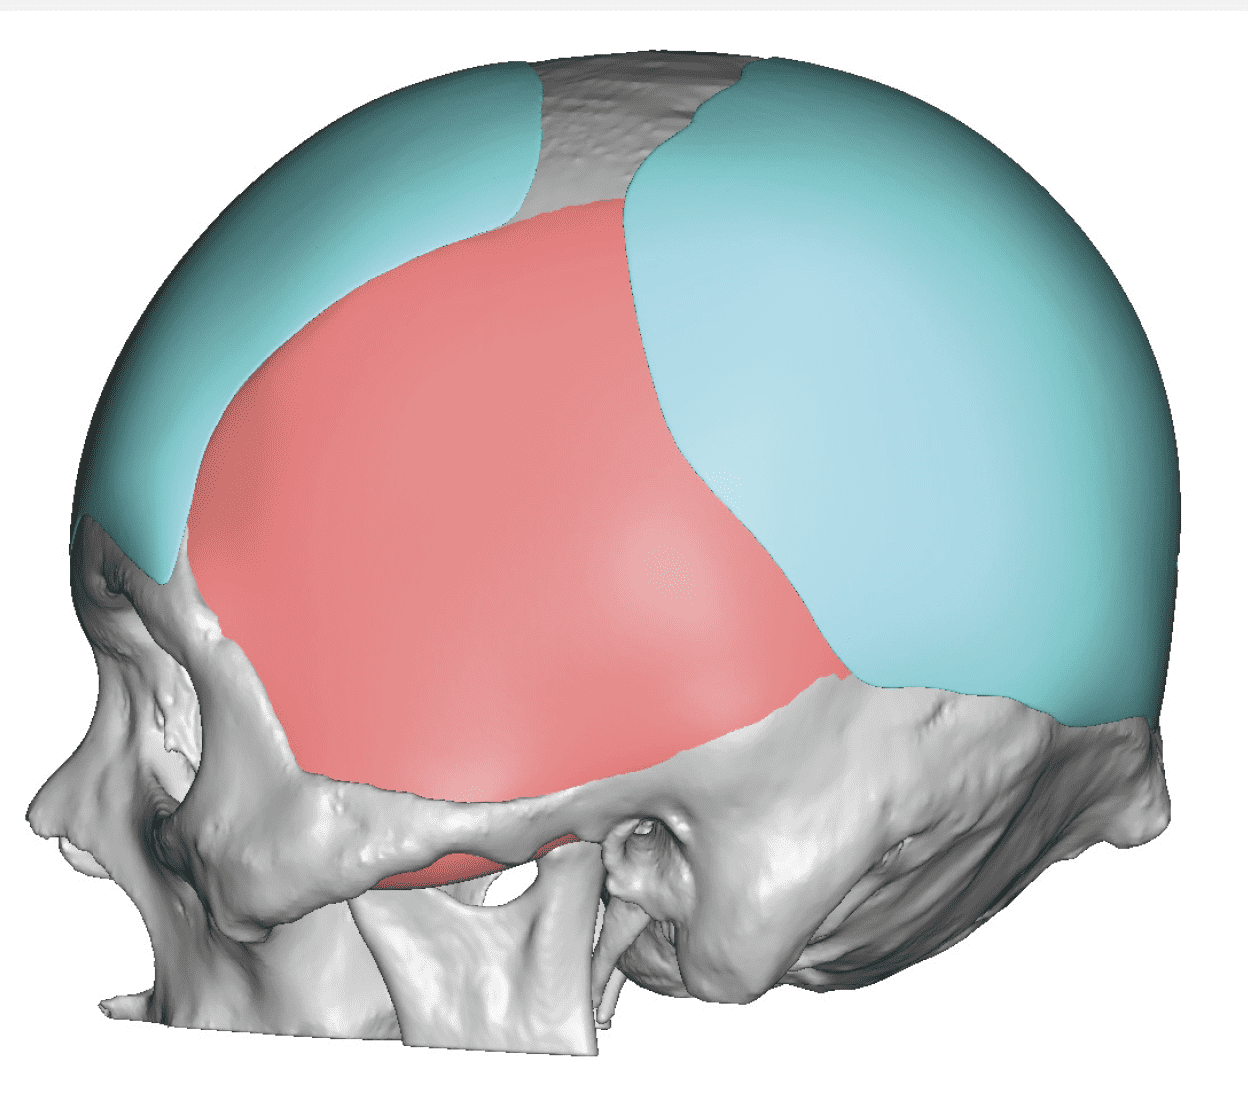

Patient 28

Desire for rounder shape to the top of the head from a congenital parasagittal deficiency skull shape.

Custom skull implant designed to fill in the parasagittal deficiencies.

Desire for rounder shape to the top of the head from a congenital parasagittal deficiency skull shape.

Custom skull implant designed to fill in the parasagittal deficiencies.